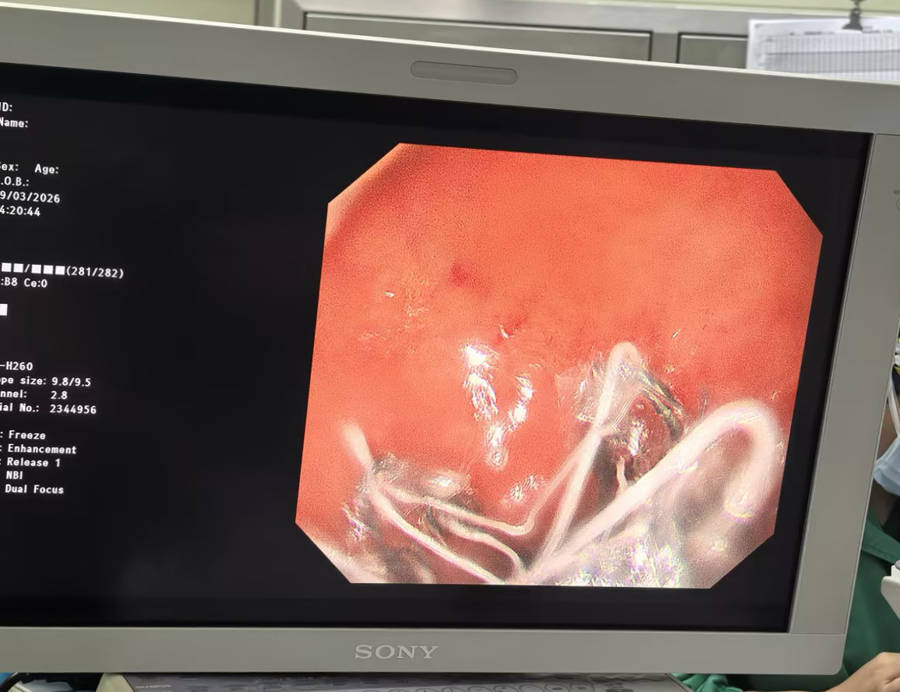

术中,团队借助先进的内镜设备,精准地将长约60cm的胃转流支架置入十二指肠及空肠上段,从而隔离食糜和十二指肠/近段小肠黏膜,减少小肠绒毛上皮细胞对营养的吸收。手术顺利开展,全程患者生命体征平稳。术后第四天,患者顺利出院。3个月后,将来院行胃镜下胃转流支架取出术。